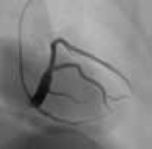

CAROTID STENTING MODULE:

PROcedure Rehearsal Studio Ready!

This module includes 12 virtual patient cases, providing practice on all aspects of the carotid stenting procedure, including distal or proximal protection system placement, angioplasty and stenting. Learners may experience complications such as spasm and baroreceptor response. Patient anatomy varying in arch types, locations of strictures and varying degrees of stenosis.